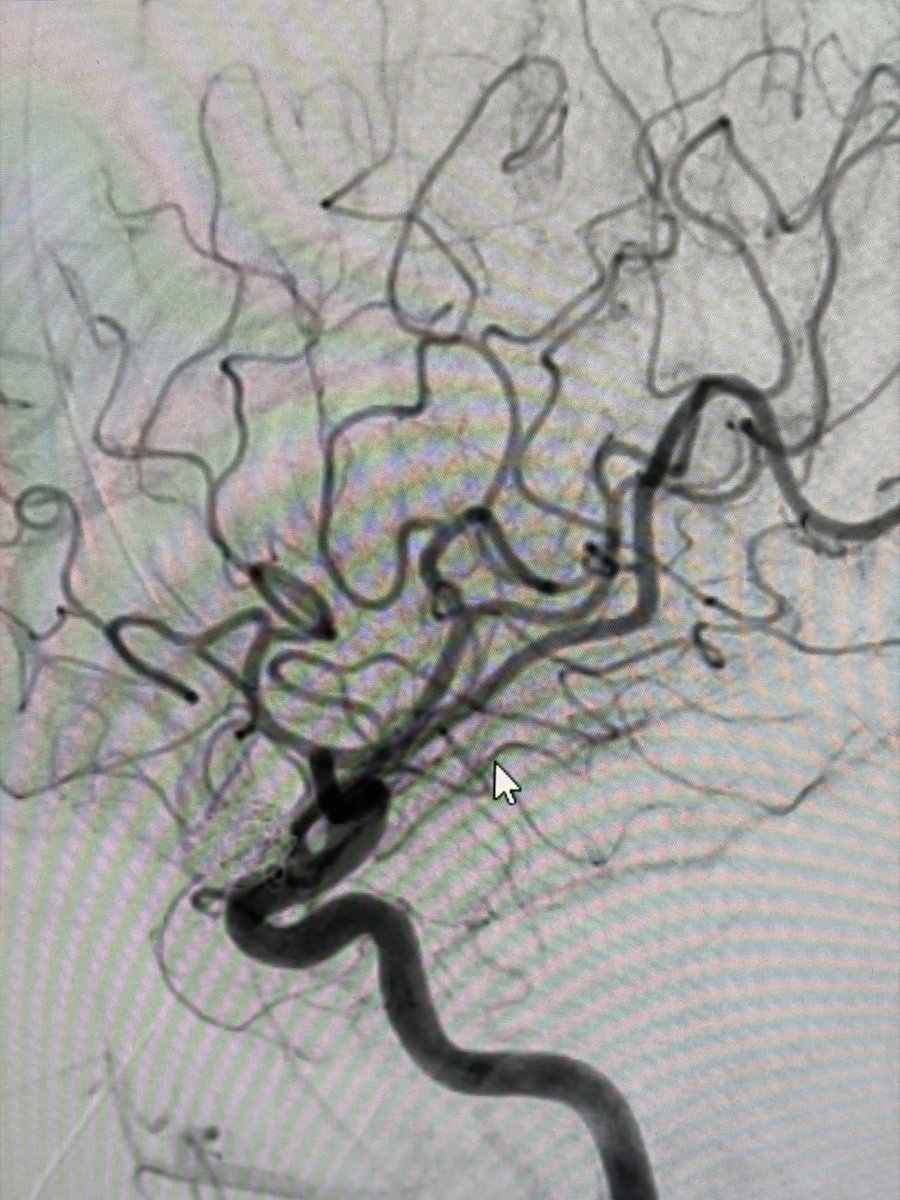

Two weeks ago, a 54-year-old patient recovering from open-heart surgery (CABG) suffered a major stroke. • Symptoms: Sudden inability to speak + right-side paralysis. • Action: Immediate Mechanical Thrombectomy to remove the brain clot.

Manish Kumar Yadav tweet mediaManish Kumar Yadav tweet mediaManish Kumar Yadav tweet mediaManish Kumar Yadav tweet media